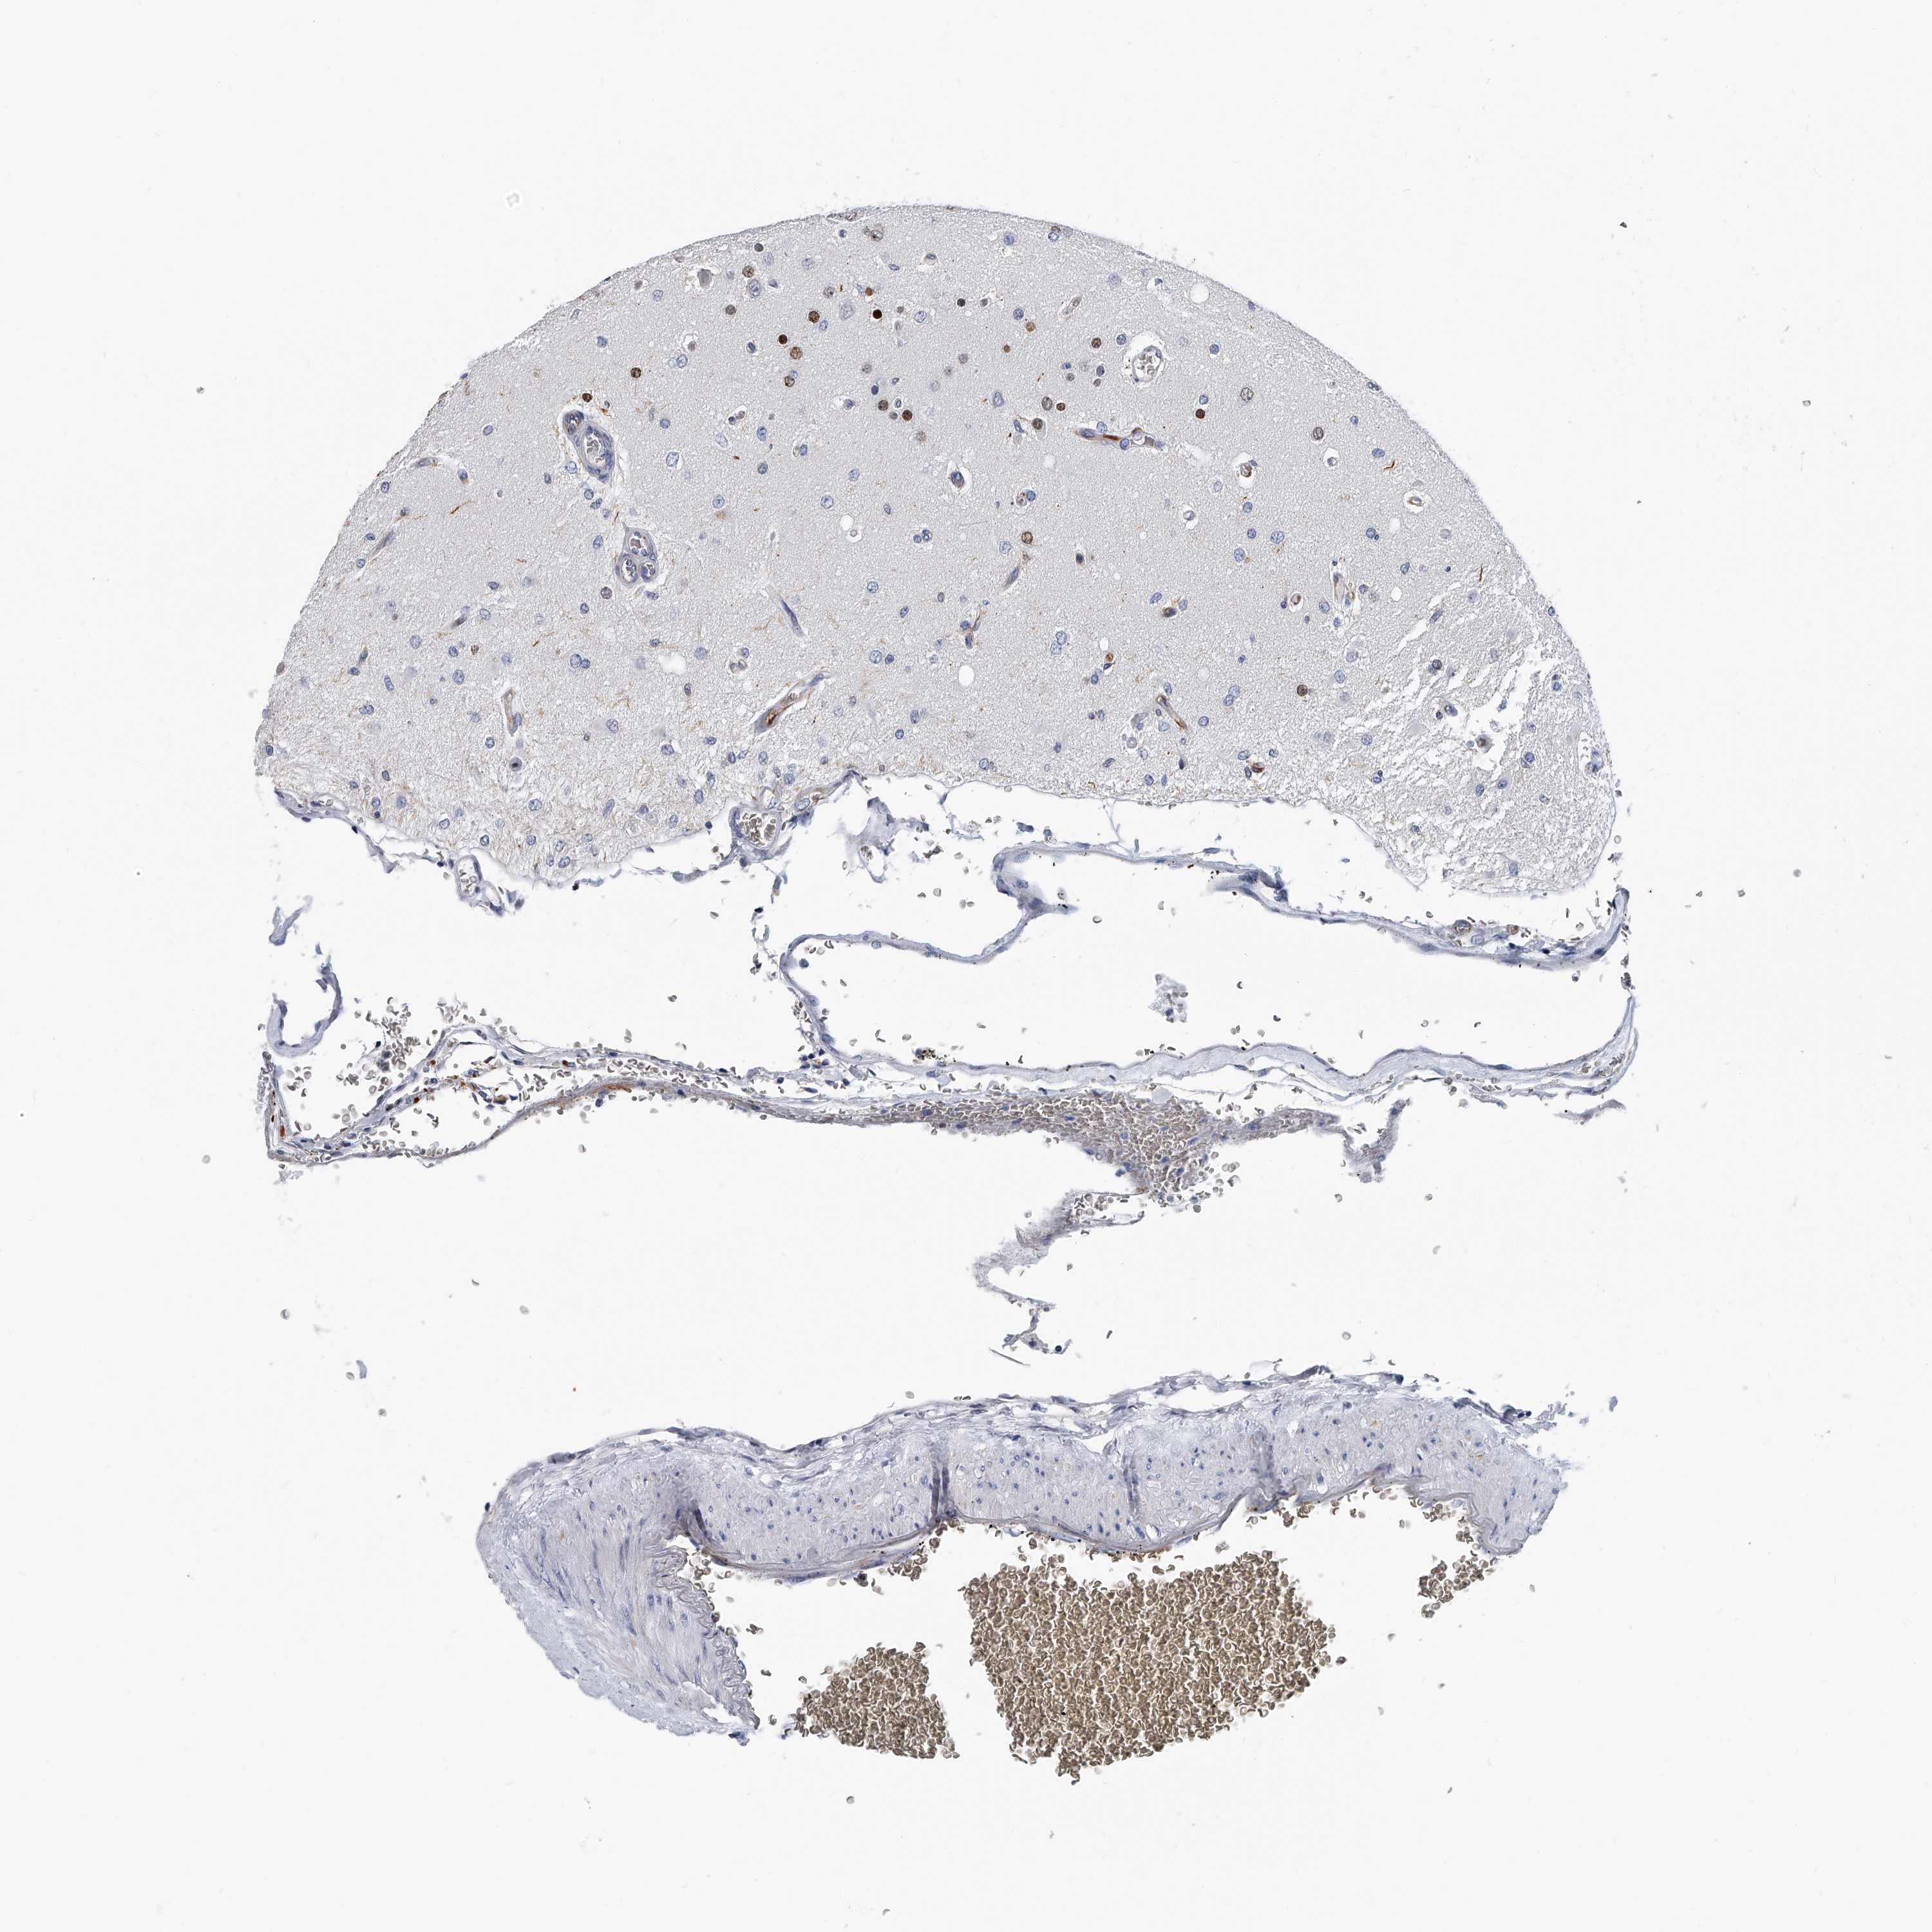

GLIOMA - Protein expressioni

A mouse-over function shows sample information and annotation data. Click on an image to view it in a full screen mode. Samples can be filtered based on level of antibody staining by selecting one or several of the following categories: high, medium, low and not detected. The assay and annotation is described here.

Note that samples used for immunohistochemistry by the Human Protein Atlas do not correspond to samples in the TCGA dataset.

Antibody stainingi

Antibody staining in the annotated cell types in the current human tissue is reported as not detected, low, medium, or high, based on conventional immunohistochemistry profiling in selected tissues. This score is based on the combination of the staining intensity and fraction of stained cells.

Each image is clickable and will lead to virtual microscopy that enables deeper exploration of all samples and also displays staining intensity scores, fraction scores and subcellular localization as well as patient and tissue information for each sample.

Antibody HPA030458

Staining

High

Medium

Low

Not detected

Intensity

Strong

Moderate

Weak

Negative

Quantity

>75%

75%-25%

<25%

None

Location

Nuclear

Cytoplasmic/membranous

Cytoplasmic/membranous,nuclear

Glioma, malignant, High grade

Glioma, malignant, Low grade

Glioblastoma, NOS